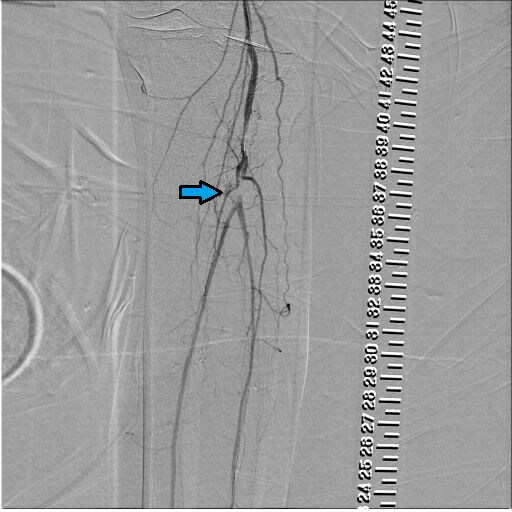

図8.BK Pre画像

Pop以遠の造影。Popに狭窄、trunk(矢印部)とATAの閉塞が認められる。